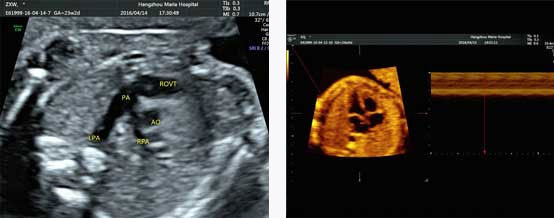

四维彩超能排查遗传性综合征等胎儿早期疾病。多角度观察宫内胎儿的生长发育情况,为早期诊断胎儿先天性体表畸形先天性心脏疾病提供科学依据。

真实呈现胎儿胎心结构、脐带、血流变化

四维彩超优异的图像分辨率,能在四维空间内展现立体的心脏结构和功能,不仅能够检测高危孕妇的心脏状况,h's检查胎儿心脏发育情况。

四维彩超具备一整套成熟的胎心成像技术,支持从胎儿心脏结构到心功能的专业分析,是胎儿心脏检测评估领域的技术。双平面成像技术可实时观察胎心结构和血流变化,帮助临床医生及时作出诊断。